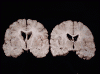

Pathology of the cases:

The area of necrosis is

indicated by the white arrows. The infarcted area includes the insula, the upper

temporal lobe and lower frontal-parietal lobe on one side. The pathologic

findings are most consistent with non-hemorrhagic infarction resulted from

unilateral obstruction of the middle cerebral artery (MCA).